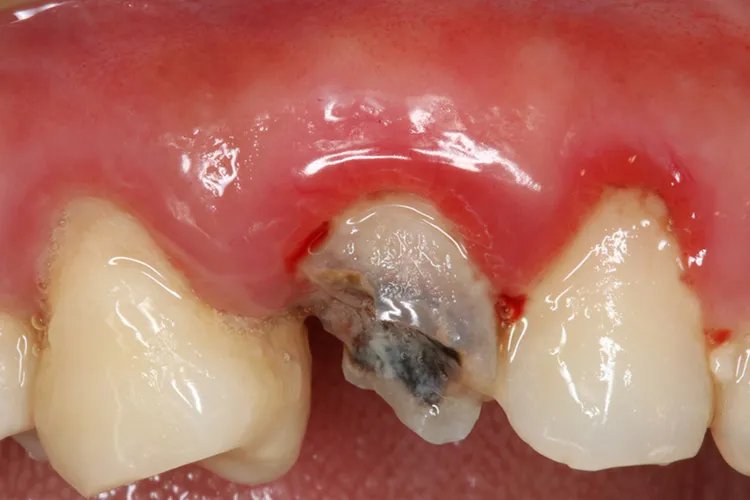

外形缺损是龋齿最显著的临床特征,形成了牙体组织的实质性缺损。临床上可以看到、探到或检查到龋洞。

质地的改变龋造成的牙体组织的实质性缺损称为龋洞。龋洞中充满感染脱矿的牙体组织和食物碎屑,质地松软,容易与正常组织区别。

患者感觉的变化当龋损发展到牙本质层并出现龋洞时,才有冷热刺激或食物崁塞时的敏感症状,但都是一过性的,刺激消失,症状随之消失。当龋发展至牙本质深层时,症状会明显一些。病因发生龋齿的原因主要是由于具备了致龋菌和致病的牙菌斑环境,同时口腔中含有细菌代谢的底物,当酸或致龋物质聚集到一定浓度并维持足够时间时,就会发生龋。诊断龋齿的诊断以患者对患牙的感觉为基础,对患牙进行检查。使用不同型号不同大小的探针,可以发现早期的窝沟龋和发生在邻面的龋。在视诊和探诊不能确定龋损的情况下,应拍摄X片。光学检查、电导检查、龋损组织化学染色等对龋齿的诊断也有一定的作用。治疗龋齿的治疗应对个案进行分析,制定治疗计划。考虑患者目前的主要问题,及时终止病变的发展,做好预防和保护。对于已经有龋洞应尽可能去除坏死组织,封闭龋洞,修复龋损,恢复功能。